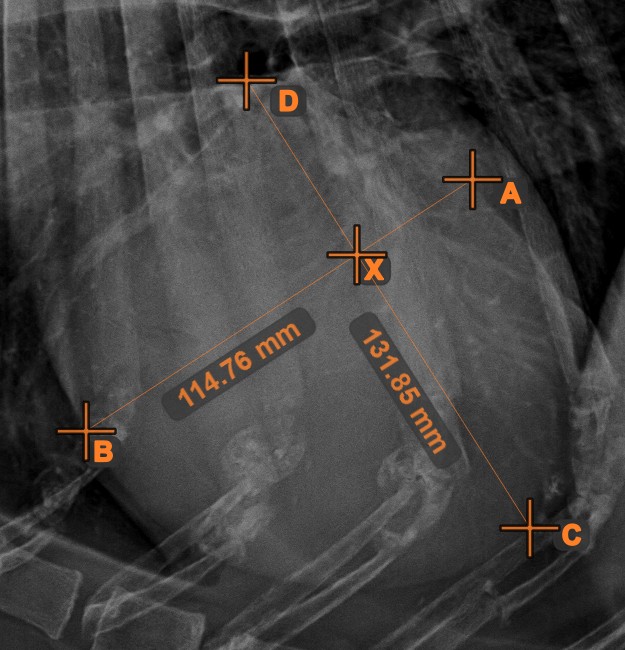

Line Intersection¶

Quickly and accurately locate and mark the intersection point between two existing lines by using the Line Intersection

tool.

Select the tool from the left toolbar and assign it to one of the available mouse buttons. Select two lines that have already been drawn on the scene to complete the measurement. The intersection point of the line will be automatically calculated and marked on the scene. The intersection point of two lines will always be marked with the letter X.

Information

If two lines do not intersect directly, the intersection point of their extended projections on the scene will be marked.

Line Measurement¶

Select the Line Measurement

tool and assign it to one of the available mouse buttons. Place the start and end points on the scene or select them from already existing points on the image. The distance between the two points will be automatically

calculated by using the default calibration data, or the recalibrated data by the length calibration measurement.